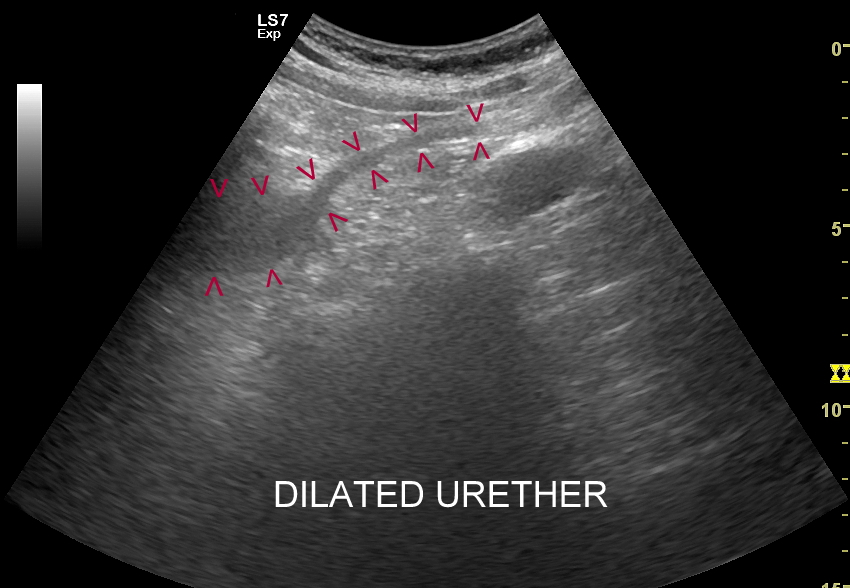

Objawy kolki nerkowej wynikają z mechanicznego drażnienia i wtórnego ranienia ścian moczowodu w trakcie przemieszczania się kamienia, a ich lokalizacja zależy od miejsca, w którym aktualnie złóg się znajduje. Najczęściej może on utknąć w naturalnych zagięciach i przewężeniach moczowodu, tj. na złączu miedniczkowo-moczowodowym, na skrzyżowaniu moczowodu z naczyniami biodrowymi oraz przy pęcherzu moczowym. W omawianych warunkach dominują zasadniczo bóle o charakterze ostrym. Druga przyczyna objawów związanych z kolką nerkową wynika z zastoju moczu oraz podwyższonego ciśnienia w układzie kielichowo-miedniczkowym; w tym wypadku dominują bóle tępe.

Badania obrazowe służące wykrywaniu kamicy moczowej to badanie RTG, CT, lecz przede wszystkim badanie USG. W badaniu USG nerek w prezentacji B kamica nerkowa widoczna jest w sytuacji, gdy złogi są odpowiednio uwapnione, odpowiednio duże oraz nie zlewają się z zatoką tłuszczową miedniczki nerki. Zasadniczo złogi w trybie B będą widoczne wyraźniej, gdy położone są w miąższu nerki; z kolei w miedniczce nerkowej, gdy są na tyle duże, że dają artefakt cienia. Czasem w celu uwidocznienia złogu przydatne jest wyłączenie wspomagania typu x-beam.